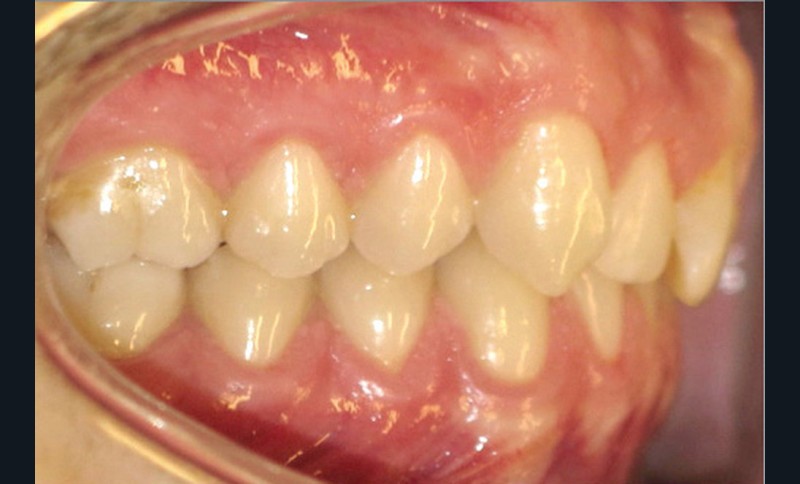

Examen endobuccal (fig. 2a-e)

L’arcade maxillaire est asymétrique, en hémi-lyre droite. Elle présente une mésio-position du secteur 1 en lien avec un encombrement antérieur estimé à 4 mm, se traduisant par une palato-position de la 12 et une rotation de la 11. On observe également des mésio-rotations des premières molaires et une palato-version incisive. L’arcade mandibulaire est ellipsoïde et présente un léger encombrement incisif (1 mm).

Concernant les relations occlusales, on observe une classe II complète subdivision droite. Le surplomb est absent et le recouvrement augmenté, estimé à 4 mm, a provoqué une usure des bords libres de 11 et 21 par attrition. Dans la dimension transversale, on constate une endoalvéolie maxillaire, ainsi qu’une concordance des médianes incisives entre elles, mais toutes deux déviées à droite par rapport au plan sagittal médian.